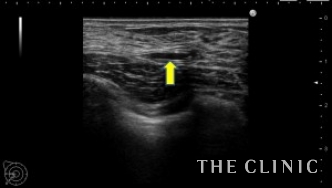

エコーでは右に6cmを超えるしこり(オイルシスト)、左にも3.5㎝のしこり(混合性のしこり)、小さなオイルシストも認めました。

左;オイル成分もありますが半分以上は充実性成分です。